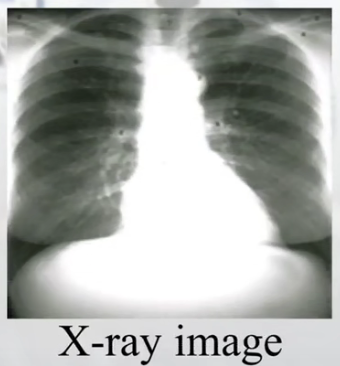

(6)X光(X-ray):

(3)X-ray图像:很好描述肺结构